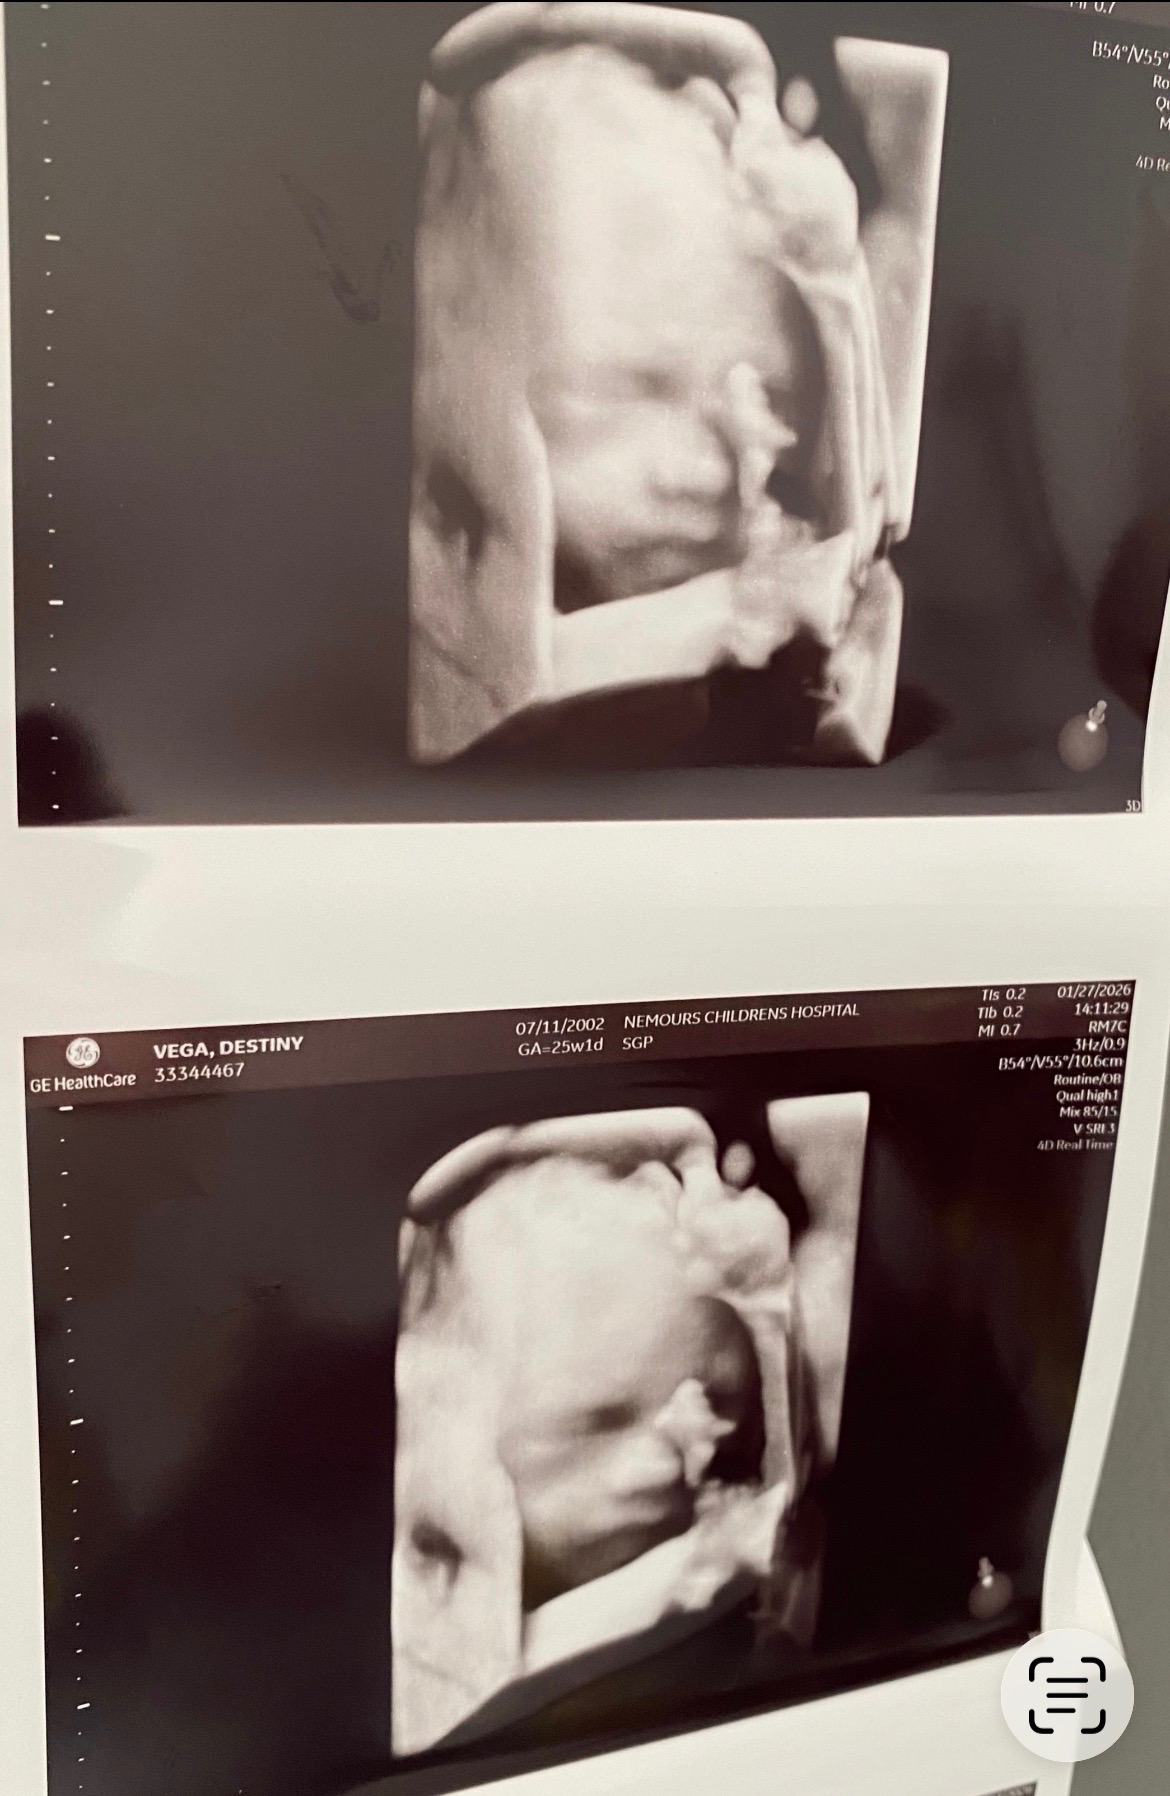

I’m reaching out as a very hopeful and loving soon to be Gigi. Destiny’s water broke early at 29 weeks, and she has been admitted to the hospital so she and baby boy can be closely monitored. The goal right now is for baby to keep growing until 34 weeks, when it will be safer to deliver him. Thankfully, they are both stable right now, and we are taking things one day at a time with faith and gratitude.

If you feel led to give, share, or pray for them, it would mean more than words can express. Most of all, we ask for continued prayers over this sweet baby boy, and that he continues to grow strong and healthy.